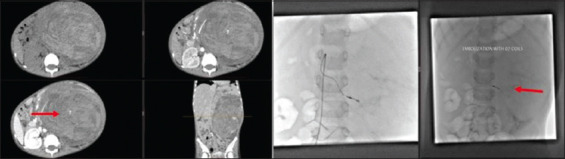

Case description: A previously healthy 5-year-old boy with no significant past medical or surgical history presented to the clinic with gradually worsening abdominal distension associated with occasional abdominal pain, gross hematuria, and lethargy for four months. Diagnostic investigations showed an 18-cm left-sided metastatic (pulmonary) renal tumor (Wilms), which was deemed unresectable on imaging. Treatment was planned according to the SIOP-RTSG protocol. However, he became hemodynamically and vitally unstable with acute, sudden distension of the abdomen on the left side after the first cycle of chemotherapy. Imaging showed active bleeding from an inferior branch of the left renal artery. Selective angioembolization was done, and chemotherapy was reinitiated with a patent left main renal artery. Following the fourth cycle of chemotherapy, he developed hemodynamic instability and abdominal pain; imaging revealed the resolution of pulmonary nodules and bleeding from the left renal artery (main); this was again embolized, and the patient was stabilized. The patient was operated on after optimization, and a complete resection of the mass was done with negative margins. On six months follow-up, he is well.